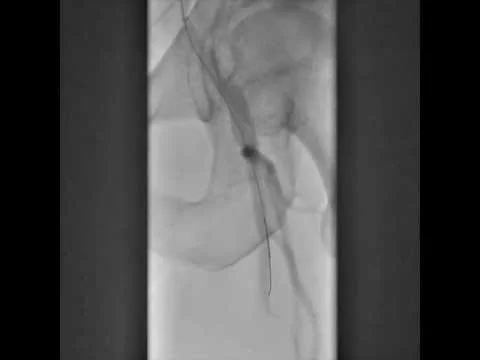

Engaging SFA CTO